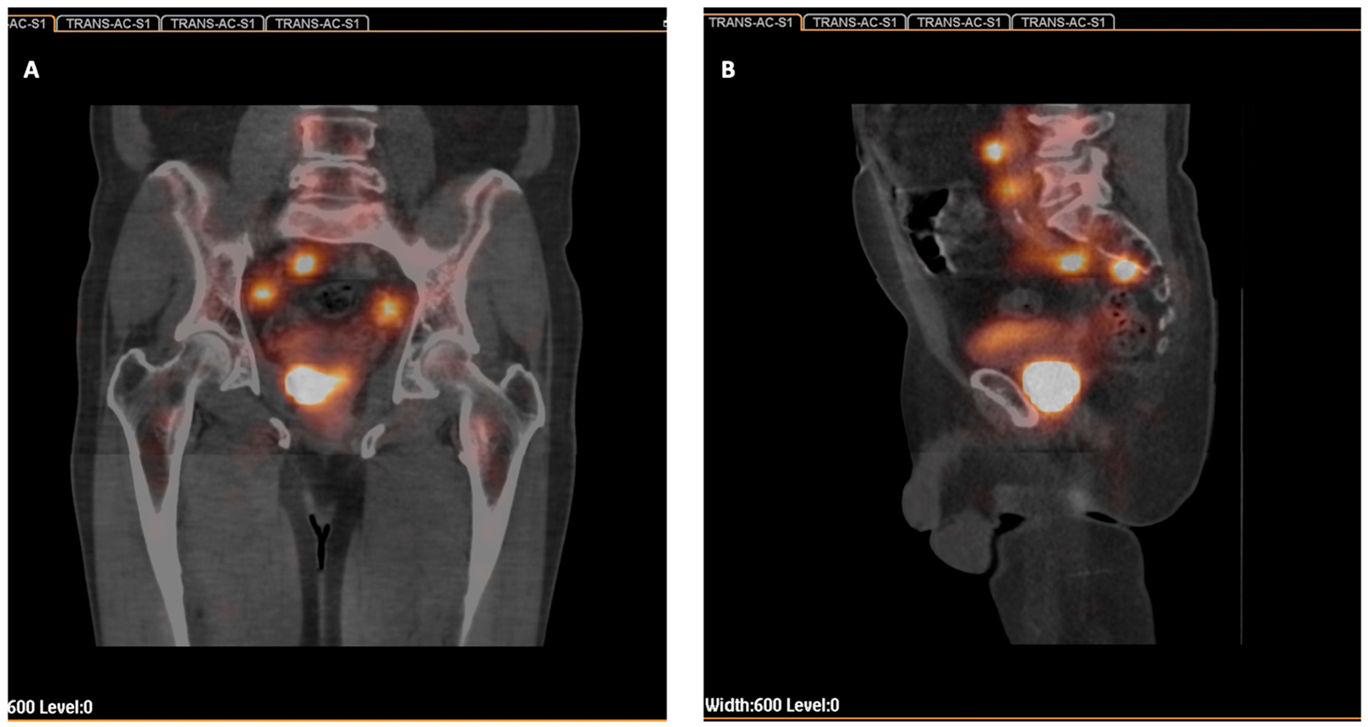

2.2. Radiocolloid Injection and SPECT-CT Imaging